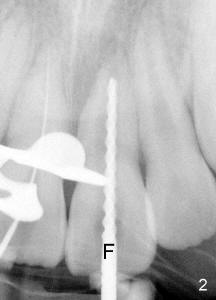

2. Use a rubber dam, debride the root canal system using intra-canal instruments (files, Fig.2: F), and irrigatge with NaOCl (bleach)